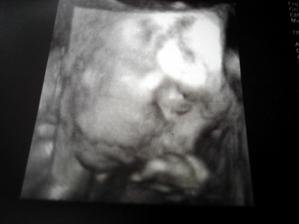

28.1.09 Zátěžový test - glykémie (OGGT), 3D ultrazvuk - sestřička se moc snažila, ale mimčo se pořád schovávalo, ručičky dávalo před obličej. Máme video 45min. a 3 fotky, tak snad z toho něco vzejde🙂)